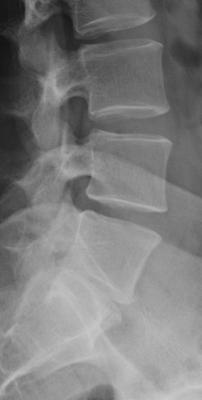

Kann mir mal jemand die Röntgenbilder interpretieren?

Habe starke Schmerzen beim Heben von Lasten und bei langen gebückten Arbeiten. Ich hoffe Ihr könnt mir helfen! MfG Daniel

- forum_photo1.jpg (7.78 KiB) 9693 mal betrachtet

- forum_photo.jpg (8.93 KiB) 9693 mal betrachtet

Offenbar handelt es sich bei der ersten Aufnahme um eine frontale Aufnahme, die eine Skoliose zeigt.

Die zweite Aufnahme ist wohl eine seitliche Aufnahme, leider in einem sehr begrenzten Bereich, und zeigt eine Hyperkyphose (Rundrücken).

Hallo Klaus,Klaus hat geschrieben:Die zweite Aufnahme ist wohl eine seitliche Aufnahme, leider in einem sehr begrenzten Bereich, und zeigt eine Hyperkyphose (Rundrücken).

Die Zweite Aufahme ist eine Teilaufnahme der Lendenwirbelasaule und sagt daher nichts ueber den Gradzahl der Brustwirbelsaeule aus.

Wir sollten warten bis alle Ergebnisse da sind, so dass man erkennen kann wo die Hauptbaustelle sitzt. Es scheint in der Tat so zu dein dass ueber dem Kreuzbein die BWS recht verschlissen ist aber die anderen Untersuchungen koennen da Klarheit bringen. CT und MRT scheint mir zienlich doppelt gemoppelt aber ich bin da kein Experte.